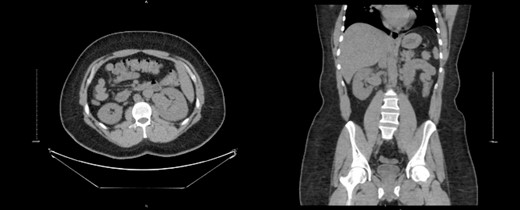

A 32-year-old male with no known chronic illnesses had a history of a motor vehicle accident five years ago, resulting in multiple bilateral rib fractures. An abdominal and pelvic CT scan conducted at the time did not reveal any other findings. The patient was admitted under the care of thoracic surgery for observation and pain management. After four years from the accident, the patient experienced intermittent right flank pain and made multiple visits to the emergency room. A CT scan of the kidneys, ureters, and bladder (CT KUB) was performed to rule out urolithiasis. The CT KUB showed multiple prominent structures with communication between the arterial and venous systems at the right renal hilum, suggestive of an intrarenal AVM with no apparent complications (Fig. 1). A CT run-off study confirmed the presence of an intrarenal AVM in the upper pole, measuring 2.9 cm (Fig. 2). The patient underwent angioembolization; however, multiple attempts at coil embolization failed due to the high risk of distal embolization. Subsequently, the patient underwent exploratory laparotomy for right AVF ligation. During the procedure, three AVF tracts were identified and ligated using clips. Prior to ligation, a thrill was palpable, but it was absent after the ligation. On the second postoperative day, a Doppler renal US was performed, which revealed patent right intrarenal arteries with normal resistive indices and normal peak systolic velocity in the right main renal arteries.

CT KUB showed multiple prominent structures with communication between the arterial and venous systems at the right renal hilum, suggestive of an intrarenal arteriovenous malformation (AVM).